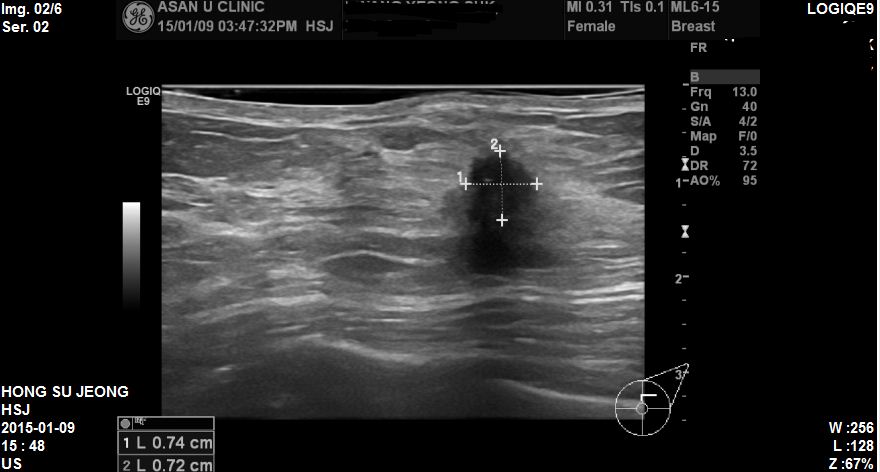

건강검진상 이상소견으로 내원하신 60세 환자분이십니다

본인이 느끼는 증상은 전혀 없었고 건강검진에서 추적검사 권유받아 내원하셨습니다.

본원 유방초음파상 좌측 11시방향에 1cm미안에 경계가 불명확한 혹이있었고

조직검사 시행한 결과 침윤성유방암으로 진단되었습니다.